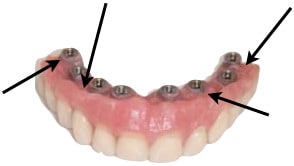

Olivier je suis d’accord sur le soin à apporter à la conception du balcon vestibulaire pour la pérennisation de la prothèse implanto portée. Les cas clinique présentés portent uniquement sur des prothèses provisoires mise en place dans le même temps chirurgical que les implants dentaires. Dans le cas suivant la conception de l’armature recouverte d’opaque autorise une retouche du balcon vestibulaire uniquement constitué de résine. Ce qui est demandé au provisoire dans un premier temps, c'est de solidariser fermement les implants entre eux pour éviter tous micros mouvements. Lors de la première dépose après cicatrisation, il est possible d’ajuster le balcon vestibulaire. Le système SynConne pour implants Ankylos consistant à solidariser une coiffe dans un appareil est validé scientifiquement.

Conception du balcon vestibulaire :

Une erreur souvent commise est un ajustement en continu du balcon à la gencive.

(Image 2)

- Le balcon doit être affleurent à la gencive.

- Un dégagement supérieur doit être aménagé en regard des implants

(Image 3)

- Un dégagement supérieur doit être aménagé autour des implants

(Image 4)

Si ces points ne sont pas respectés une accumulation va se produire sans pouvoir dans un premier temps être dégagée de façon naturelle par le flux salivaire, puis par un nettoyage mécanique.

La solution est de dégager des zones d’évacuation quitte à sacrifier l’esthétique comme l'a montré growler dans une autre discussion.